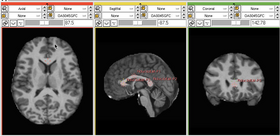

Caption 1

Caption 2

Caption 3

• Example Test: Shows an example of segmenting the brain ventricles in an MR volume of brain